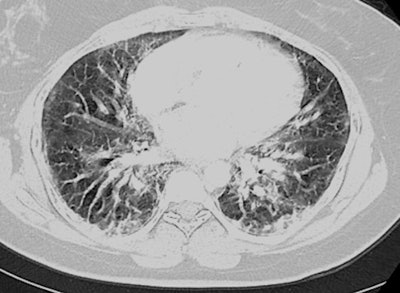

Two days following discharge, the patient returned to the emergency department with worsening symptoms. Chest CT scans revealed signs consistent with diffuse alveolar damage -- including extensive opacification of the lung parenchyma with interstitial edema -- which is a common mechanism of injury for ARDS. The patient had no previous medical history but reported having used e-cigarettes for about two to three hours per day, three times a week over the past year. Confirming EVALI in the patient convinced the clinicians to send her to another medical center for oxygenation.